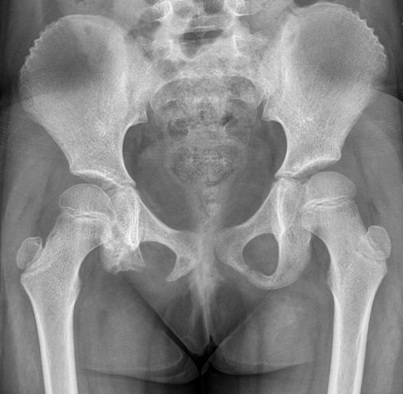

Langerhans cell histiocytosis is a multi system disorder with a certain predilection for involving hypothalamic pituitary axis. We hereby report a 7 year old girl presenting with polyuria, polydipsia and growth retardation. The girl had a past history of pain in right hip joint and nodular region over chest. Water deprivation test confirmed the diagnosis of central diabetes inspidus. Other investigations revealed Growth hormone deficiency and central hypothyroidism. X-ray and MRI hip revealed absent right inferior pubic ramus with bone marrow biopsy confirming the diagnosis of histiocytosis. Patient was treated with nasal Arginine Vasopressin spray, subcutaneous growth hormone and oral thyroxine.